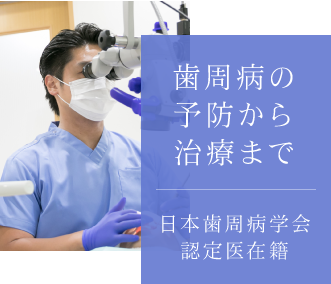

大学病院との連携や、

認定医による

専門性の高い診療

近隣の大学病院と連携をとりあうことで、難度の高い治療や専門的な検査・診断にも対応。

また、歯周病認定医である院長による専門的な知識・治療技術を活かした歯周病治療をはじめ、ホワイト二ングコーディネーター資格を持つ歯科衛生によるホワイトニング治療をご提供いたします。

20代で約7割・

30~50代で約8割の人が患っている歯周病はお口の健康だけでなく全身に影響

歯周病は痛みがないまま重症化しやすく、日本人が歯を失う原因第一位。恐ろしいのはそれだけでなく、歯周病菌によって心疾患や早産・低体重児出産などの全身疾患の発症リスクが高まるほか、糖尿病とも密接に関係することがわかっています。

当院では歯周病の予防をはじめ、認定医による治療で難症例まで幅広く対応。歯ぐきが下がった、という方もご相談を。